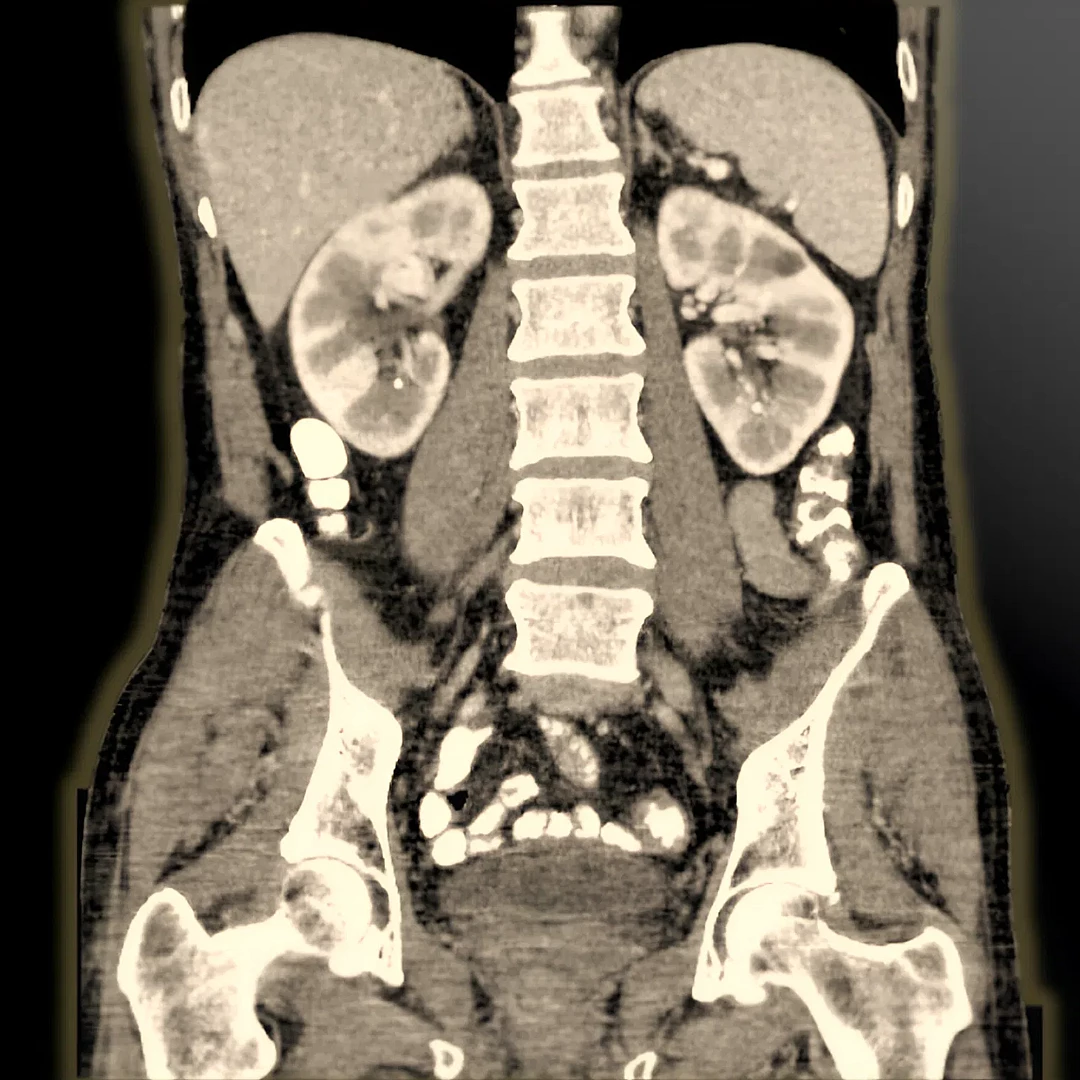

Abdomen and Pelvic CT provides detailed cross-sectional images to diagnose conditions affecting the liver, kidneys, intestines, bladder, and reproductive organs. It’s a fast and accurate tool for evaluating pain, infections, or tumors in the abdominal and pelvic regions.

CT Urography provides detailed imaging of the kidneys, ureters, and bladder to detect stones, tumors, or urinary tract abnormalities. It’s a fast, contrast-enhanced scan ideal for comprehensive urinary system evaluation.